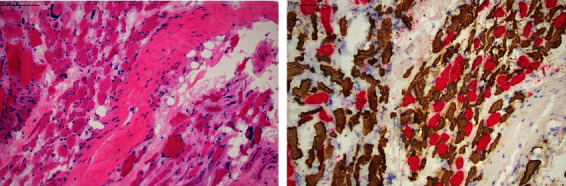

A 24-year-old Indigenous Australian female with long-standing, poorly controlled type 1 diabetes mellitus (T1DM) presented with 3 months' history of unilateral thigh swelling and pain. Her laboratory investigations showed evidence of a persistent inflammatory state with normal creatine kinase. Infectious and autoimmune investigations were negative. Imaging demonstrated evidence of muscular oedema and atrophy. Muscular pain and swelling have a broad list of differential diagnoses. This case highlights a rare but potentially debilitating complication of diabetes mellitus-diabetic myonecrosis with its challenges in reaching a definitive diagnosis due to non-specific symptomology and laboratory findings. However, it is an important differential of leg pain and swelling to consider, particularly in those with long-standing diabetes and pre-existing microvascular complications. Glycaemic control is paramount in preventing this potentially severe diabetic complication.

Abstract Image